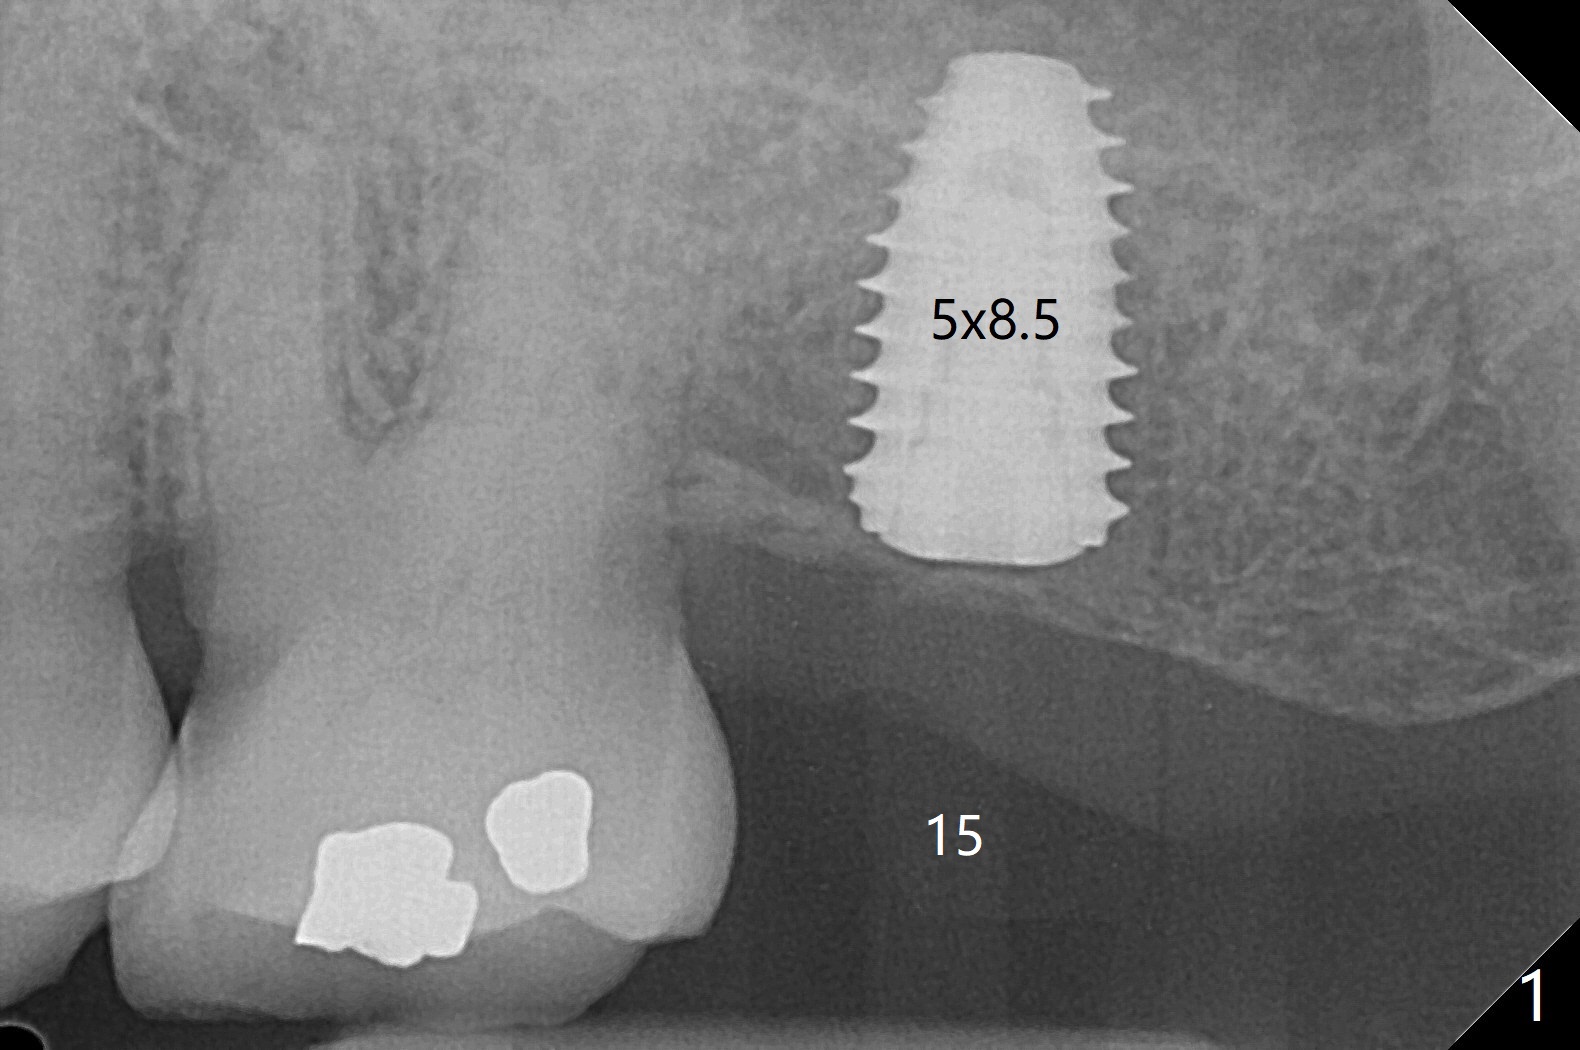

Biopsy punch is used after guide tissue punch marking at #15 because of expected low stability associated with a 8.5 mm long implant for the 73-year-old woman (Fig.1). For #18 site, the same punch is reused with reduced sharpness and some trauma to the tissue. After implant placement (Fig.2), the osteotomy appears to invade the buccal nonkeratinized gingiva. The saved tissue returns to the sites with perio glue fixation and perio dressing. The dressing at #18 is loose 2 weeks postop. When it is removed, the wound seems to be healing (Fig.3). The dressing at #15 remains stable 2 weeks postop (not removed).